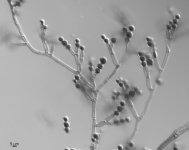

| Species Name: | Scopulariopsis brevicaulis |

| Taxonomy: | FUNGI Ascomycota, Sordariomycetes, Microascales, Microascaceae |

| Substrate: | skin biopsy of cutaneous lesion, male 26 yr with non-Hodgkin's lymphoma who underwent unrelated bone marrow transplant; histopathology + for numerous fungal hyphae in deep dermis | Location: | USA Nebraska, Omaha, University of Nebraska Medical Center (GEO: 41.255,-95.976) |

| Characters: | HUMAN/ ANIMAL PATHOGEN invasive cutaneous infection in patient with non-Hodgkin's lymphoma - fide P. Iwen // HUMAN/ ANIMAL PATHOGEN invasive cutaneous infection in patient with non-Hodgkin's lymphoma - Iwen PC, Schutte SD, Florescu DE, Noel-Hurst RK, Sigler L, Med Mycol 2012 Epub Apr 23 (Click for publications citing UAMH 10915) |